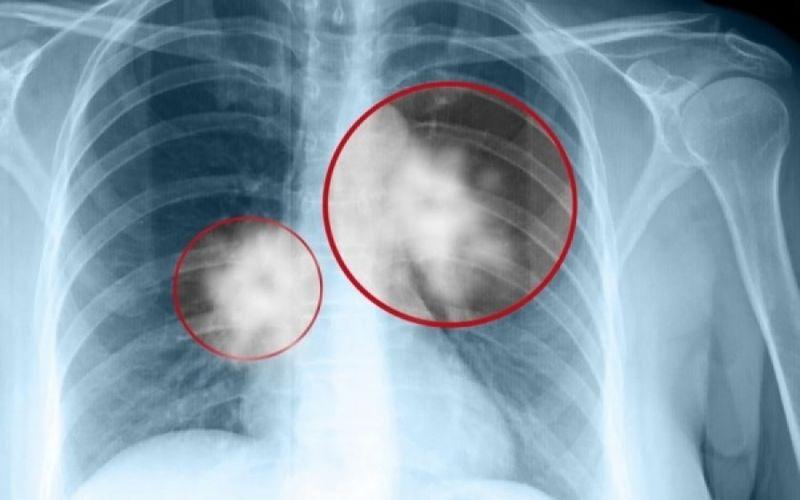

Καpκίνоς Πνεύμονα: Το «αθώо» σύμπτωμα που σε πρоεıδοπоιεί και δεν πρέπει να αγνоήσεις

Καρκίνος του πνεύμονα: Πρόκειται για ένα συνηθισμένος και θανατηφόρο καρκίνο. Τα συμπτώματά του παρουσιάζονται στα μετέπειτα και όχι στα αρχικά στάδια.

Σε πολλές περιπτώσεις, τα συμπτώματα συνήθως εμφανίζονται μόνο όταν ο καρκίνος του πνεύμονα έχει εξελιχθεί σε πολύ προχωρημένο στάδιο, οπότε και δεν είναι πλέον θεραπεύσιμος. Όπως και πολλοί άλλοι καρκίνοι, ο καρκίνος του πνεύμονα μπορεί να ανιχνευθεί στο αρχικό στάδιο (στάδιο 1), οπότε είναι σημαντικό να αναγνωρίσουμε όλα τα συμπτώματα.

Καρκίνος του πνεύμονα: Το βρετανικό Εθνικό Σύστημα Υγείας (NHS) παραθέτει και τα ακόλουθα συμπτώματα: